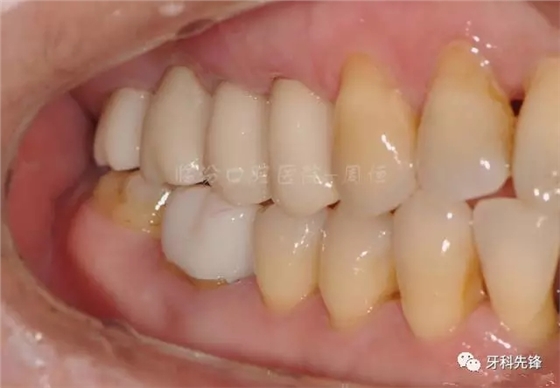

圖2 術(shù)前側(cè)位咬頜照

640.webp (3).jpg